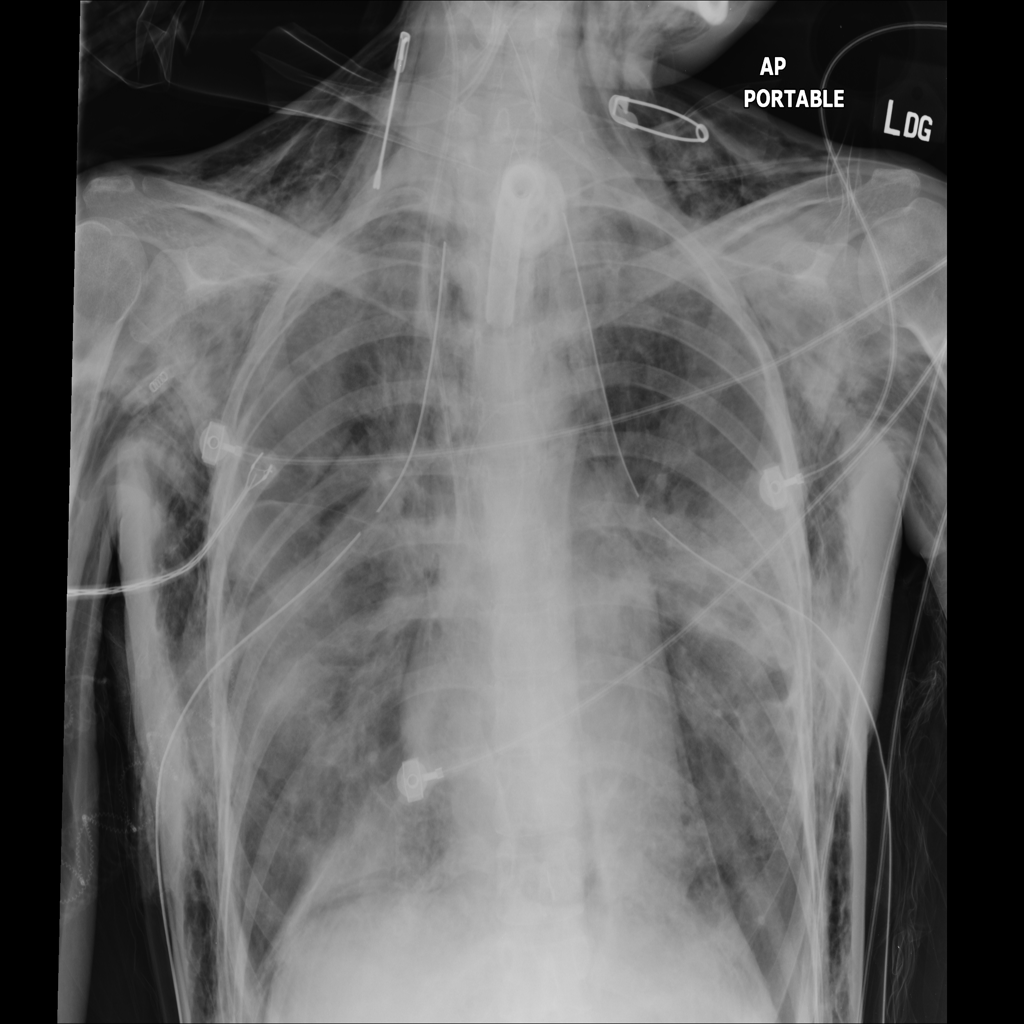

PAT-0E82 · IMG-000Emphysema

PAT-0E82 · IMG-000

AP